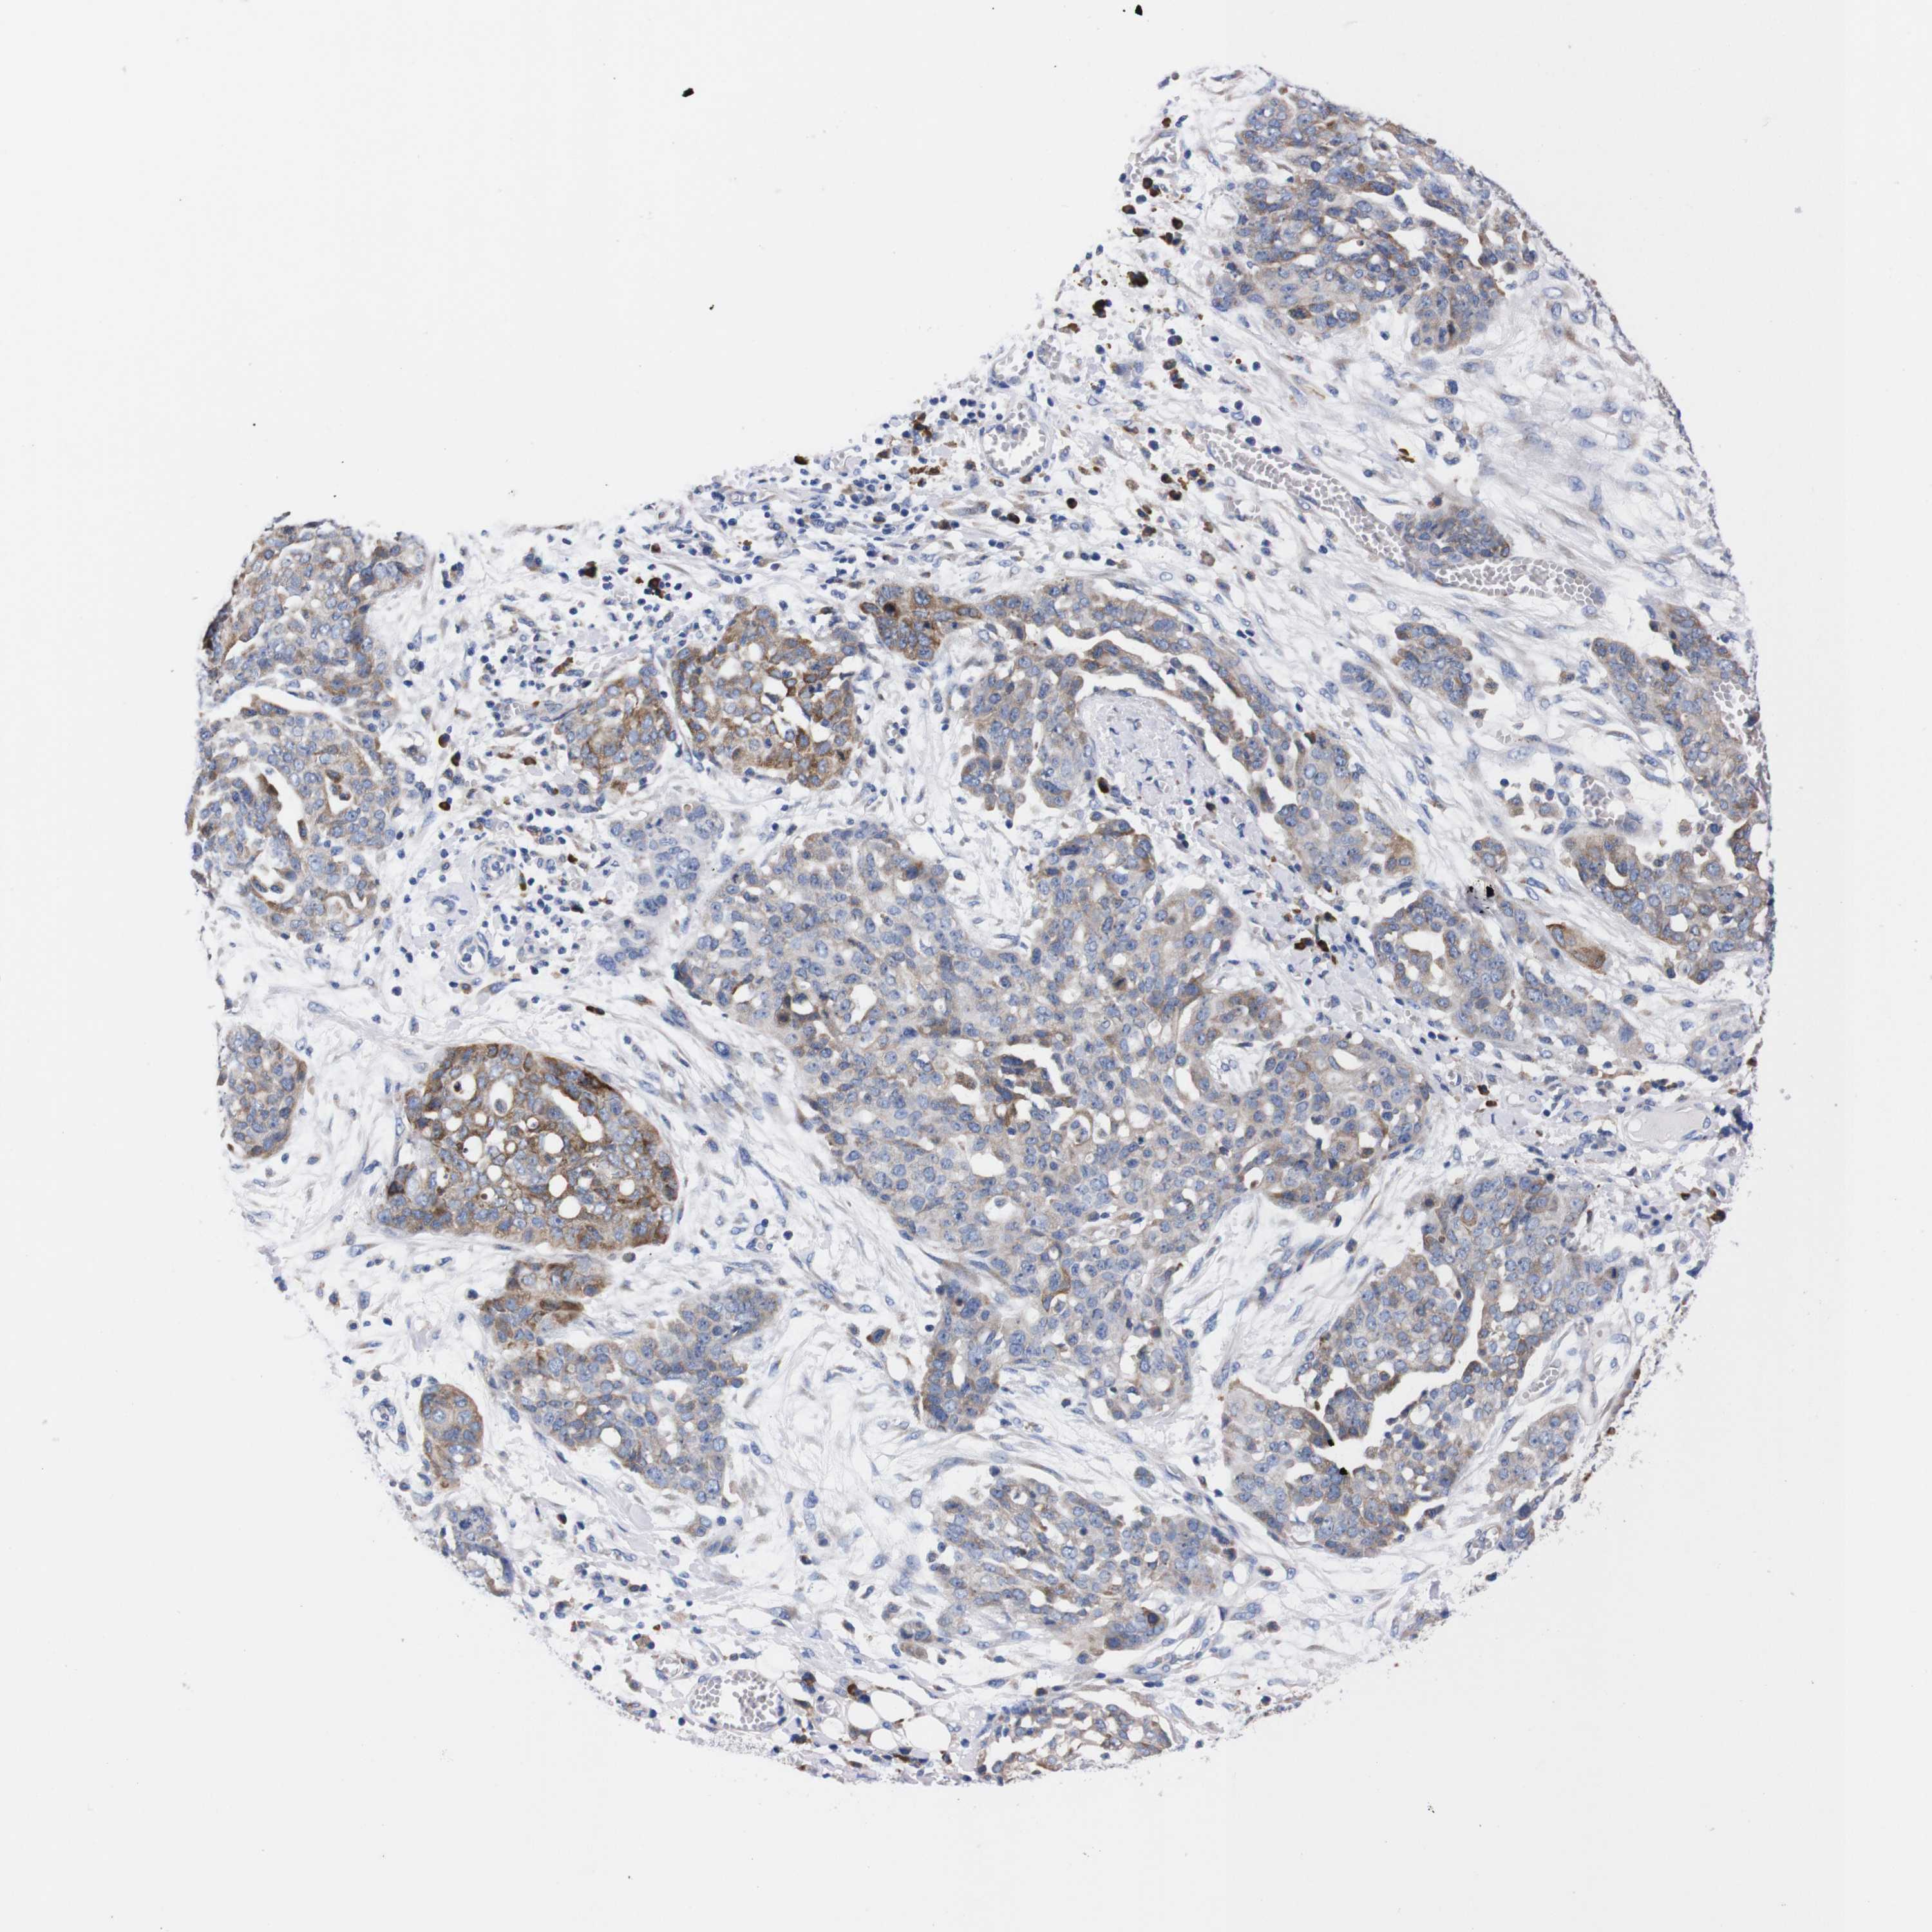

OVARIAN CANCER - Protein expressioni

A mouse-over function shows sample information and annotation data. Click on an image to view it in a full screen mode. Samples can be filtered based on level of antibody staining by selecting one or several of the following categories: high, medium, low and not detected. The assay and annotation is described here.

Note that samples used for immunohistochemistry by the Human Protein Atlas do not correspond to samples in the TCGA dataset.

Antibody stainingi

Antibody staining in the annotated cell types in the current human tissue is reported as not detected, low, medium, or high, based on conventional immunohistochemistry profiling in selected tissues. This score is based on the combination of the staining intensity and fraction of stained cells.

Each image is clickable and will lead to virtual microscopy that enables deeper exploration of all samples and also displays staining intensity scores, fraction scores and subcellular localization as well as patient and tissue information for each sample.

Antibody HPA013994

Antibody HPA013995

Cystadenocarcinoma, serous, NOS

Carcinoma, endometroid

Cystadenocarcinoma, mucinous, NOS

Carcinoma, NOS